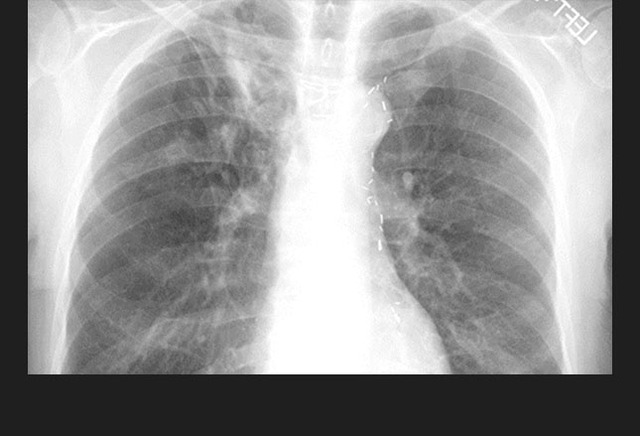

图1. 一位进展性肺结核患者双侧胸腔积液(左侧较右侧严重)。

影像学特征包括斑片状或肺叶的实变、空洞(继发性肺结核的典型表现)、纵隔淋巴结肿大和胸腔积液。继发性肺结核常侵犯上叶尖后段及下叶背段。代表着血行播散的粟粒型肺结核并不常见,但预后不佳。